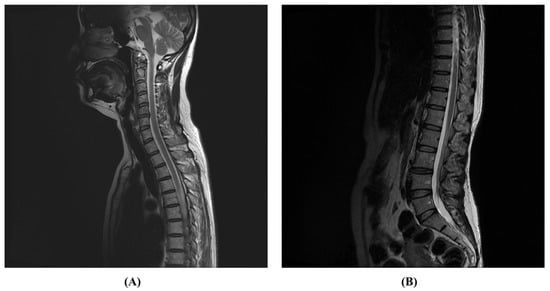

2. Case Presentation